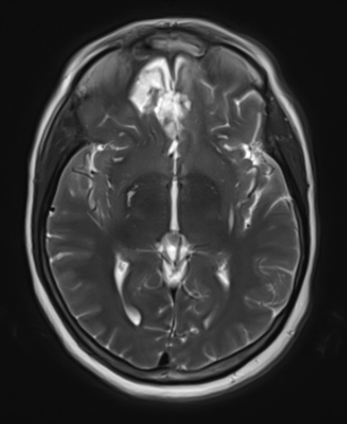

Figure 1b – Postoperative MRI demonstrating a complete resection without residual enhancement.

She was started on high-dose steroid and antiseizure prophylactic medicine. Surgical intervention was offered for mass effect, symptomatic relief, neurologic preservation, and histopathologic diagnosis. Dr. Gaudin performed a bifrontal craniotomy with complete resection of neoplasm through an interhemispheric and subfrontal approach. Postoperative imaging demonstrated a gross total resection without residual tumor and resolution of mass effect (Figure 1b and 2b). Intraoperative pathology was consistent with meningioma, WHO grade 1. She recovered very well, and was discharged home on postoperative day 3. On her follow-up outpatient visit, her preoperative symptoms had fully resolved, and her olfactory sense was maintained.